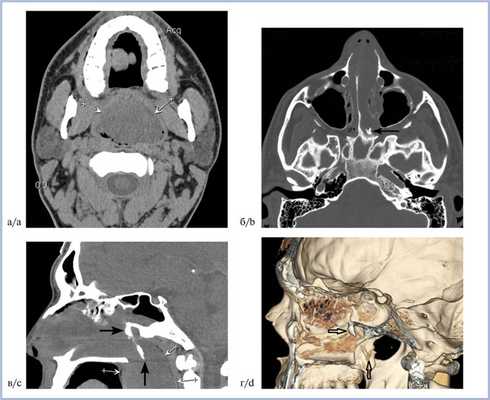

С целью диагностики пациенту была выполнена КТ околоносовых пазух (рис. 1, а—г). Рис. 1. КТ околоносовых пазух пациента Л., 30 лет, до операции. а, б — аксиальная плоскость; в — реконструкция в сагиттальной плоскости; г — 3D-реконструкция в режиме «костного окна». Образование носоглотки, распространяющееся из левой клиновидной пазухи через расширенное естественное соустье (белые стрелки); костный шип, растущий из свода носоглотки и состоящий из двух фрагментов, соединенных узким костным «мостиком» (контурные стрелки). По данным КТ было обнаружено образование мягкотканной плотности больших размеров, полностью заполняющее просвет носоглотки и распространяющееся через хоану в левую половину полости носа (см. рис. 1, а, в). Естественное соустье левой клиновидной пазухи было резко расширено, через него образование проникало в саму пазуху (см. рис. 1, в). В своде носоглотки, чуть ниже расширенного соустья клиновидной пазухи, визуализировался костный шип, который вместе с мягкотканным образованием опускался в носоглотку до уровня твердого неба (см. рис. 1, б—г). Обращало на себя внимание то, что шип состоял из двух фрагментов, соединенных между собой узким «мостиком» (см. рис. 1, в, г). Общая длина шипа достигала 35 мм.

Пациенту в связи с невозможностью выполнения эндоскопического оперативного лечения за счет гигантских размеров новообразования было выполнено его удаление через рот при помощи окончатых щипцов Юраша для носоглотки под местной поверхностной анестезией 10% лидокаином (рис. 2). Рис. 2. Макроскопическое оперативное изображение удаленного полипа. Полип серо-желтого цвета, плотноэластической консистенции, длиной 14 см (в расправленном состоянии), шириной от 3 до 7 см, толщиной 3 см. А — часть полипа, обтурирующего клиновидную пазуху; В — ножка полипа; С — часть полипа, расположенная в носоглотке. По данным макроскопического исследования: новообразование плотноэластической консистенции, по внешнему виду напоминает полипозную ткань.

Послеоперационный период протекал без особенностей, носовые кровотечения не рецидивировали. Больной был выписан на 5-е сутки в удовлетворительном состоянии без каких-либо жалоб. Результаты контрольной КТ показали, что образование в носоглотке тотально удалено, в своде носоглотки сохранился небольшой фрагмент ножки полипа, в которой дифференцировался небольшой остаточный костный шип (рис. 5 а, Рис. 5. КТ околоносовых пазух пациента Л. после операции. а, б — реконструкция в сагиттальной плоскости. Образование носоглотки удалено, в своде носоглотки визуализируется фрагмент ножки полипа, в котором виден небольшой костный шип (стрелки). б).